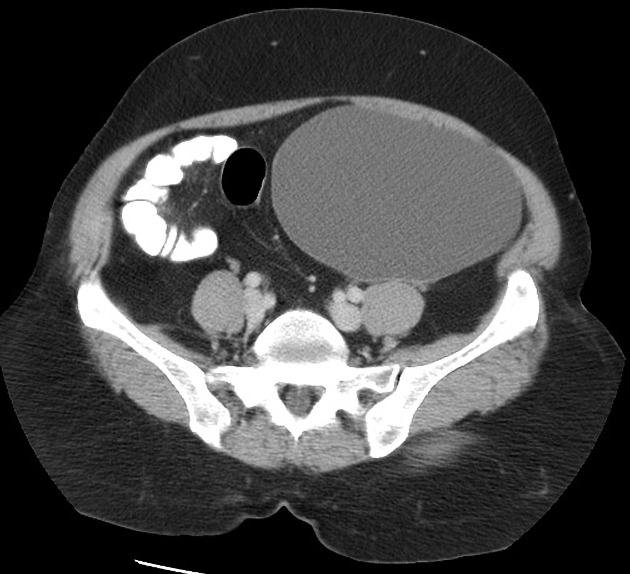

КТ не является базовым исследованием для диагностики кистомы яичника, потому что не обеспечивает достаточной детализации структуры содержимого, толщины капсулы и степени васкуляризации образования. Приоритетным методом диагностики является магнитно-резонансная томография органов малого таза. МСКТ выявляет следующие анатомические признаки:

В нативном режиме определяется округлое или овальное гиподенсивное образование с чёткими краями в проекции придатков.

В режиме сканирования мягких тканей визуализируется тонкая капсула, возможные кальцинаты в её составе и участки плотности в перегородках.

В режиме с контрастированием отмечается умеренное или слабое накопление контраста в стенке и перегородках, что отражает васкуляризацию.

В режиме высокоразрешающего сканирования костных структур уточняется взаиморасположение образования с тазовыми костями при больших размерах опухоли.

- Размер образования с точной оценкой в трёх плоскостях.

- Наличие плотных включений и кальцинатов в капсуле.

- Васкуляризация стенки и перегородок при контрастировании.

- Отношение кистомы к мочевому пузырю, матке и кишечным петлям.

- Оценка свободной жидкости в брюшной полости при подозрении на осложнение.

- Оценка возможных метастатических изменений в брюшине и лимфоузлах при подозрении на осложнённое течение.

- Наличие признаков сдавления или смещения соседних органов.